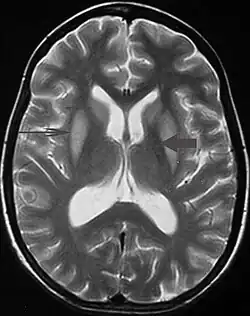

T2 weighted magnetic resonance scan image showing bilaterally symmetrical hyperintensities in caudate nucleus (small, thin arrow), putamen (long arrow), with sparing of globus pallidus (broad arrow), suggestive of extrapontine myelinolysis (osmotic demyelination syndrome)